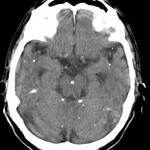

[画像診断]くも膜下腔の油性造影剤について 2010-10-15